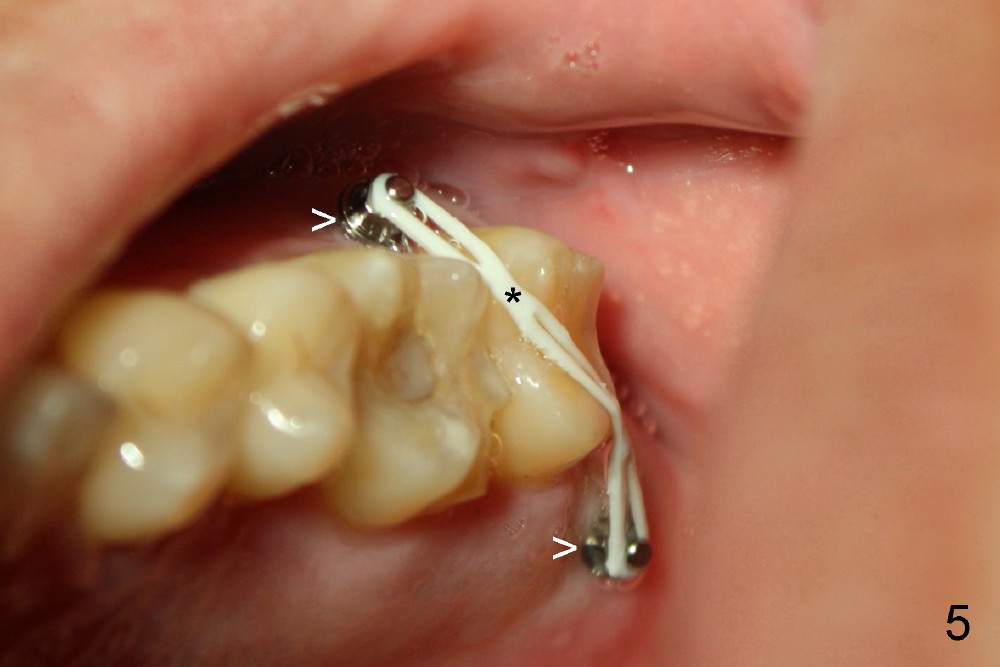

为什么那个牙冠会脱落呢?本来第二磨牙垂直高度就不足,另外似乎对合牙(图一,:15)向下面伸长(箭头),占据下牙空间,牙冠高度不够,最好方法便是使用微型植牙(图五箭头)和橡皮筋(*),持续对对合牙施加压力,它慢慢地往上移动(intrusion)。刚四十岁的冷先生对新鲜事物容易接受,正好他的保险还保这项治疗(局部矫正)。两个月后,牙齿移位不少(图六),总共四个月我们目的达到了(开始做牙冠):其实矫枉过正(图七),正是我们期待,不过告诉实验室做牙冠时不必使用所有间隙,让对合牙自己下降。